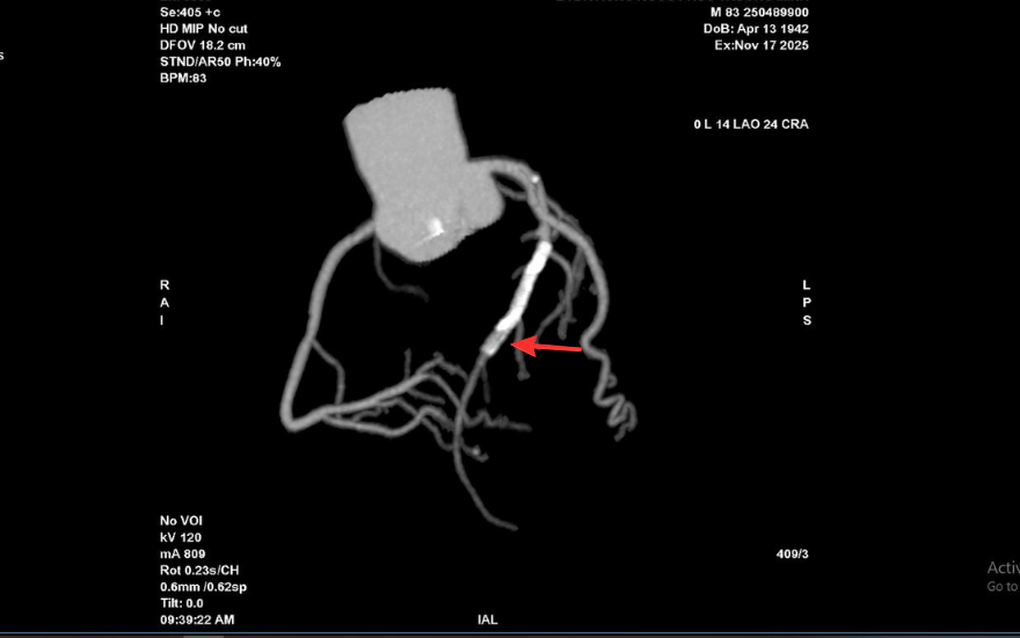

Tại Bệnh viện Đa khoa (BVĐK) Hồng Ngọc, kết quả chụp CT 2.560 lát cắt cho thấy tình trạng nghiêm trọng hơn nhiều so với biểu hiện ban đầu: mảng xơ vữa lan rộng gây hẹp nặng đoạn đầu động mạch liên thất trước và gần như làm tắc hoàn toàn lòng stent cũ. Đây là dấu hiệu cho thấy nguy cơ biến chứng tim mạch cấp tính có thể xảy ra bất cứ lúc nào nếu không được can thiệp kịp thời.

Vị trí hẹp khít trong lòng stent cũ của ông T trên hình chụp CT mạch vành 2.560 lát cắt (Ảnh: BVCC).